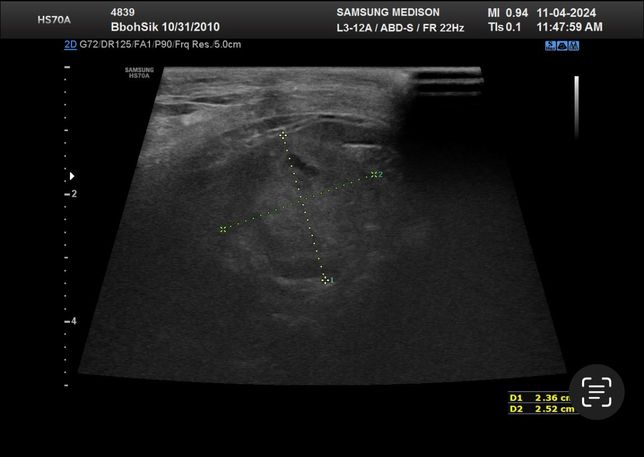

- 반려동물 건강반려동물Q. 강아지 건강검진 복부초음파에 관해서 질문드려요ㅜㅜ안녕하세요 최근 두군데에서 16살 노령견 복부초음파를 찍었습니다 그런데 두군데에서 서로 다른결과를 말씀하셔서요 한군데는 비장종괴 2.5cm 라고 하시고 한군데에서는 안커지는거보니 비장종괴가 아니라 부신종양이라고 말씀하시던데 뭐가 맞는지 모르겠어서요ㅠ 전에 초음파 찍은게 잇엇던거 같은데 사진 둘중에 뭔지는 잘 모르겟지만 혹시나 아시면 알려주실수있으실까요ㅜㅜ